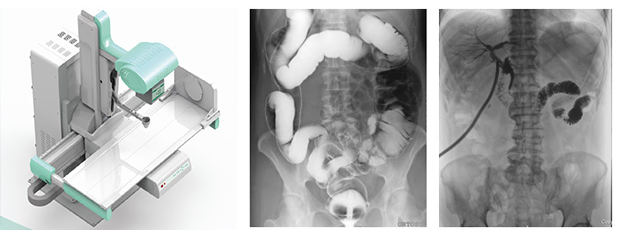

一、新一代动态平板探测器,一机多用实现动静态采集

只需一块动态平板探测器,即可高效轻松实现摄影、透视和造影功能,几乎可以满足医院全科室的临床检查需求。

1)大视野无遗漏

17*17英寸的高清像素动态平板探测器,能对胸部、腹部等部位实现大范围全覆盖,动静态之间无感切换。透视检查无须对患者重新定位便可观察到足够大的人体器官组织,避免漏诊误诊。更好地减少了曝光时间,也减少了病人的辐射剂量。

大尺寸动态平板技术,覆盖检查面积范围广,轻松实现胃十二指肠等大面积造影,无需移动即可观看整个动态过程,避免噪点对图像的影响。

2)图像质量无畸变,无失真

高效动态平板技术,图像不会有几何畸变,提供高分辨率和精确的图像,为临床诊断提供精准依据。